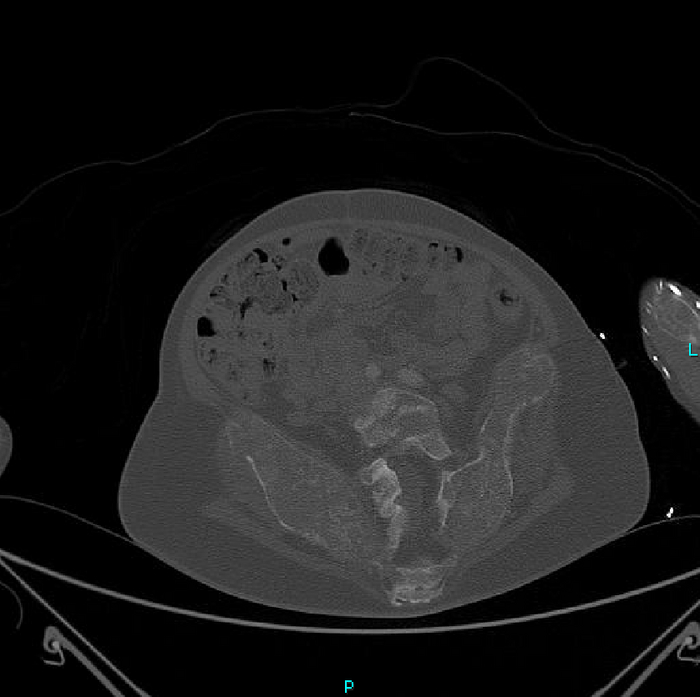

Но вернёмся к случаю: Пациент - девочка, 15 лет. Поступила после ДТП. У нас было проведено КТ-обследование по протоколу политравмы (голова / шея / грудь / живот / таз), где свежих переломов обнаружено не было, но были непонятные леденцы с костями, а именно структура и форма костей со следами старых переломов (грудная клетка и таз с бедренными костями) и, как следствие, их деформацией + следы проведённого остеосинтеза (операция с последующей фиксацией кости тем или иным способом) обоих бедренных костей. Сегодня без пометок / стрелочек, так как картинки говорят сами за себя (всё в костном окне, и всё, что мы видим - кости):

Структура костей напоминала таковую при фиброзной дисплазии (аномалия развития костной ткани с замещением нормальной кости фиброзной тканью, не является опухолью), но, обычно, эти диcплазии возникают в одном месте, т.е. поражают 1 кость (моностотическая форма) и, намного реже, бывают множественные поражения (полистотическая форма), но не всего скелета, как в нашем случае.